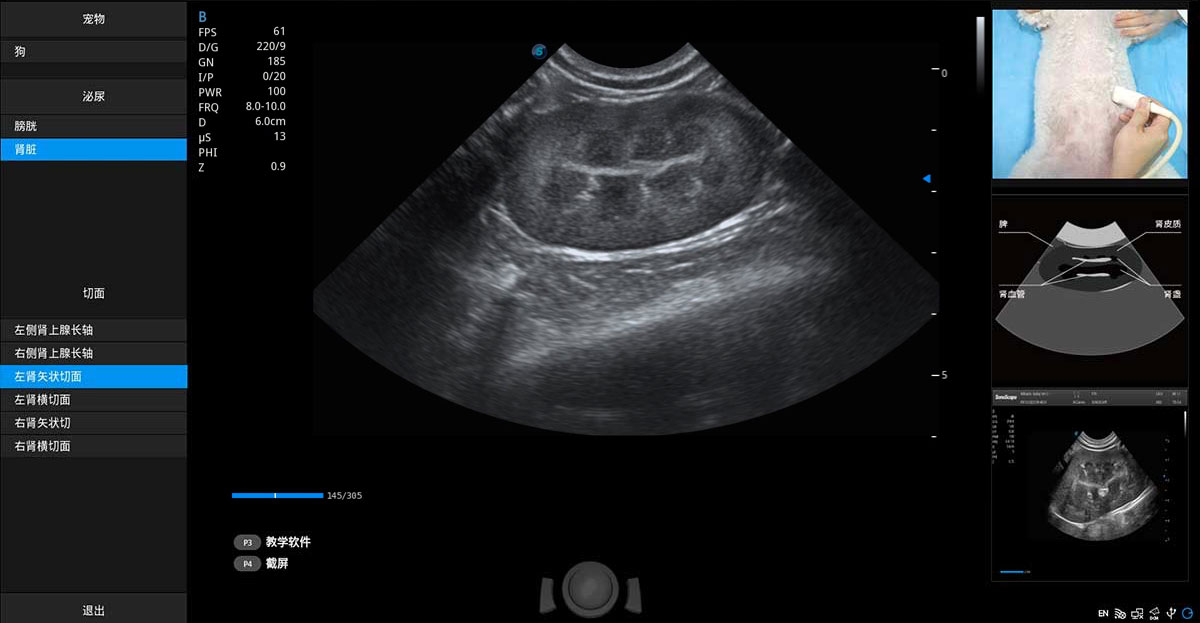

提供解剖示意圖、標(biāo)準(zhǔn)超聲圖像、掃查手法涂和操作者實(shí)時(shí)檢查圖像,指導(dǎo)操作者進(jìn)行標(biāo)準(zhǔn)切面的正確掃查。

ProPet 80 專(zhuān)為動(dòng)物醫(yī)生設(shè)計(jì),對(duì)不同的動(dòng)物體型和生理結(jié)構(gòu)作出了針對(duì)性的優(yōu)化。通過(guò)動(dòng)物影像專(zhuān)用軟件,可滿足個(gè)性化的應(yīng)用需求,幫助動(dòng)物醫(yī)生獲得更精確的診斷數(shù)據(jù)。